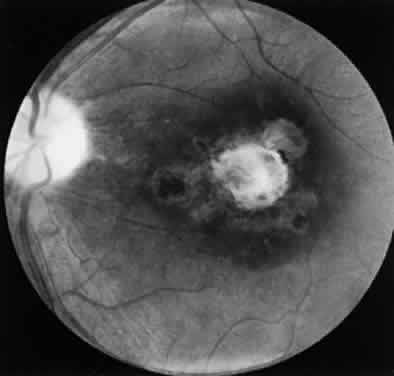

Ocular toxoplasmosis most commonly presents as a focus of necrotizing retinitis (Fig. 7) involving the inner layers of the retina and associated with a whitish fluffy lesion surrounded by retinal edema.6,59 Cells are seen in the vitreous overlying the lesion. The focus of retinitis may be large (Fig. 8) or small (Fig. 9). The retina is the primary site for the multiplying parasites, whereas the choroid and sclera may be the sites of contiguous inflammation. When the choroid is involved by the inflammatory reaction, the lesion is referred to as retinochoroiditis. The organisms are rarely seen in the choroid. The retinal lesion may be small and single or large and multiple and may reach several disc diameters in size. Large granulomas in the posterior segment of the eye frequently are seen in patients with ocular toxoplasmosis (Fig. 10). This is associated with extensive and marked vitreous reaction that precludes visualization of the retina, and the granuloma appears as a yellowish mass surrounded by a red reflex. Punctate outer retinal involvement may be seen in some patients with toxoplasmosis.60 These appear as multifocal, gray-white lesions in the deep retina and at the level of the retinal pigment epithelium accompanied by no overlying vitreous reactions. The lesions may resolve to form fine, granular white dots. This is the earliest finding seen in the rabbit models of ocular toxoplasmosis after the injection of Toxoplasma organisms in the suprachoroidal space. The lesions in the animal model may start as deep outer retinal punctate lesions that later involve the inner layers of the retina and cause the typical focus of retinochoroiditis. Involvement of the macular area is common in patients with congenital toxoplasmosis, and exudative retinal detachment may occur in severe cases. Clumps of inflammatory cells may be seen in the vitreous or over the detached posterior vitreous face. The focus of retinitis may be a manifestation of congenital toxoplasmosis or may be associated with or follow an episode of acquired systemic toxoplasmosis. Patients presenting with recurrent toxoplasmic retinochoroiditis usually are in the second or third decade, but the disorder may occur at any age. Healing of the retinitis is associated with a decrease in retinal edema and flattening of the lesion with evidence of scar formation surrounded by variable amounts of pigment (Fig. 11). The lesion may appear as a punchedout scar with underlying sclera resulting from extensive retinal and choroidal necrosis surrounded by pigment proliferation (Fig. 12), it may become a conglomerate or proliferated retinal pigment cells (Fig. 13), or it may be small and appear as a pigment clump in the retina. The retinochoroiditic scar may harbor the Toxoplasma cysts. Healing also is associated with decrease in the vitreous cells and improvement in visual acuity. Immunologic suppression is associated with recurrence of retinochoroiditis (Fig. 14). Recurrent toxoplasmic retinitis frequently appears as “satellites” or occurs adjacent to a previous scar. Old, inactive lesions often appear to be a conglomeration of previous multiple inflammatory foci (see Fig. 13).

Fluorescein angiographic characteristic of the lesion include the presence a dark hypofluorescent center of the lesion surrounded by an area of hyperfluorescence. Angiographic evidence of arterial occlusion may be observed. In patients with retinal vasculitis, dilation of the retinal vein and staining of the vascular wall are seen. The area of scar may show hypofluorescence in the early phase of the fluorescein angiography and may show late leakage around the edges of the scar. The optic nerve head may show leakage of dye with hyperflourescence in the late stages.110 Patients with retinal vasculitis also may show changes on fluorescein angiography with staining of the blood vessel wall. Indocyanine green angiography has been used in cases of recurrent toxoplasmic retinochoroiditis. Indocyanine green angiography was found to be useful in assessing the extent of the involvement of recurrent toxoplasmic retinochoroiditis and the evolution of lesions.111 In 10 of 12 eyes with recurrent toxoplasmic retinochoroiditis, indocyanine green angiography showed multiple satellite dark spots not seen by fluorescein angiography or clinical examination of the fundus.111